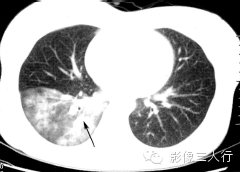

(A)平扫肺窗